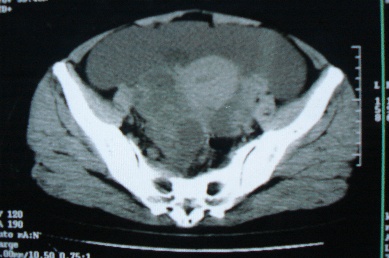

ct10755,女,48岁。感腹胀一周入院。

考虑右侧卵巢囊腺癌并腹腔转移、子宫肌瘤

感觉像是2个病变融合:双侧附件囊腺瘤?

考虑右侧卵巢囊腺癌并腹腔转移可能性大、子宫肌瘤

支持:右侧卵巢囊腺癌并腹腔转移,或囊腺瘤破裂腹腔种植。

支持:右侧卵巢囊腺癌并腹腔转移、腹水、盆腔积液。